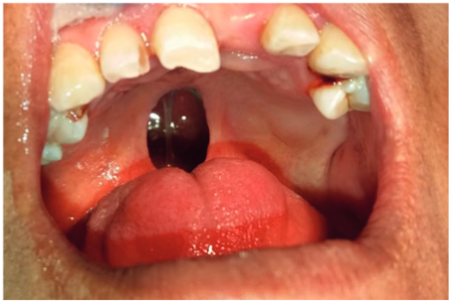

- Examen del sistema estomatognático revela fisura velo-palatina (figura 1)

Figura 1. Fisura velo-palatina

Fuente: historia clínica del paciente